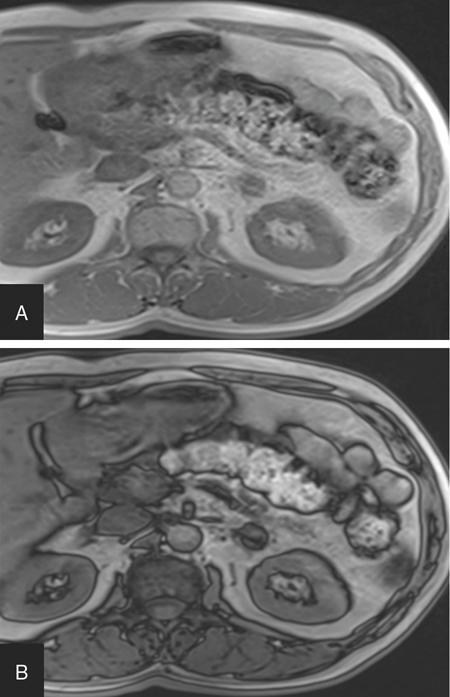

ADRENAL ANATOMY AND IMAGING TECHNIQUES Dipak Patel, Sanjay Mehta, Vishal Shah The adrenal glands (also called suprarenal/surrenal glands) are a pair of endocrine glands, retroperitoneal in location, situated superior and ventromedial to kidney on either side. Bartolomeo Eustachi described regrading adrenal in 1563 while its importance was recognized by Thomas Addison in 1855 and Brown-Séquard in 1856. It has two distinct components, the cortex and medulla, responsible for the production, release of the multiple hormones, regulating the metabolism, salt–water equilibrium in blood stream and immune system functions; besides helping body’s response to stress. Adrenal has two main parts: the cortex and the medulla. It is enclosed in complete fibrous capsule, merging with the renal capsule on either side and liver on right side. Because of lipid rich contents, cortex appears yellow. It consists of three microscopic zones. Zona glomerulosa – outer most layer, produces mineralocorticoids, largely responsible for the regulation of blood pressure; zona fasciculata – central layer, responsible for the production of glucocorticoids and zona reticularis – inner zone, thinner and darker, produces androgens. Medulla is the core of the adrenal, surrounded by the cortex and mainly found in head of the gland. It is ellipsoid in shape, grey-tan in colour and <10% of the gland volume. Greatly vascularized medulla emanates about 80% of adrenaline (epinephrine) and 20% noradrenaline (norepinephrine) (Fig. 10.16.1.1). Computed tomography (CT) histogram is another tool to unenhanced CT. It utilizes Hounsfield unit (HU) of each pixel in the given region in context of its number as well as frequency of negative pixels. It has been noted that >10% negative pixel (i.e. less than 0 HU correlate with the amount of lipid content) on histogram has sensitivity of 91% to detect adenomas accurately as compared to sensitivity of 66% on unenhanced CT scan, if used alone. Dedicated multiphasic adrenal CT protocol consists of unenhanced phase, followed by venous (about 60–90 s, after intravenous injection of nonionic iodinated contrast about 1.3–1.5 mL/kg body weight at the rate of 3–4 mL/s) and delayed (at 15 min) phases. Routinely neutral oral contrast is preferred unless indicated otherwise. Acquisition of additional arterial phase images (20–25 s) may be considered for two reasons, one for understanding adrenal arterial anatomy, may provide a guide for surgical mapping, if needed, and another to see for any hypervascular lesion like pheochromocytoma. Adrenal washout ratios are obtained using venous and delayed contrast images. (Venous and delayed phase images are required for the calculation of adrenal washout ratios.) For the evaluation of HU values, ROIs have to be placed covering at least two-thirds of the lesion, excluding areas of calcification, necrosis or haemorrhage, if any. Absolute washout = Enhanced density − Delayed density (HU) Enhanced density − Unenhanced density (HU) × 100% Relative washout = Enhanced density − Delayed density (HU) Enhanced density (HU) × 100 % Accuracy of washout calculation improves after the incorporation of unenhanced HU value (inclusion of noncontrast HU value helps in more accurate calculation of washout); therefore, whenever possible, absolute percentage wash-out (APW) should be calculated. Absolute and relative washout of about ≥60% and ≥40%, respectively, strongly suggest benign adrenal adenoma. There are certain pitfalls to washout ratios, ROI calculation may be inappropriate if it is a heterogeneous lesion with haemorrhage/necrosis and few of the lesions may show similar enhancement characteristics (hypervascular adrenal metastases, pheochromocytomas and adrenocortical carcinoma). Certain technical modifications can be applied to reduce the radiation dose and scan time, like higher pitch (should not be more than 1.5 for optimal image quality). Low-dose CT scan (LDCT) is performed with kilovoltage peak (kVp) in the range of 90–120 and mA of 40–80, particularly for lung cancer screening. According to Godoy et al., adrenal masses >2 cm (or ≥1 cm in patients with cancer history) and <4 cm in LDCT should be evaluated with adrenal protocol CT. Dual-energy CT scan (DECT) uses two different tube voltages in a single acquisition, like 140 and 80 kVp. Postcontrast and excretory phase acquisition will be done at two different tube current in single breath hold. Virtual noncontrast images have been acquired after subtraction/deduction of iodine from the contrast images. With this data set, we can calculate the contrast washout values and diagnose adenoma. Magnetic resonance imaging is a second preferred imaging modalities for assessment of adrenal disease. It has the advantage of multiparametricity, multiplanarability and high contrast-to-noise (CNR) compared to the CT scan. Chemical shift imaging (CSI) furnishes details of microscopic fat (CSI provides insight into intracytoplasmic fat). The normal adrenal appears isointense to the renal cortex on T1-weighted images and may show corticomedullary differentiation on T2-weighted images. Standard magnetic resonance imaging (MRI) protocol should provide information about the anatomical and histological characteristics of an adrenal mass (Table 10.16.1.1). Fluid component of lesion is appreciated on T2-weighted images. Pheochromocytoma appears hyperintense compared to other lesions. Diffusion-weighted images (DWIs) – Apparent diffusion coefficient (ADC) value of adenoma and metastatic lesion show considerable overlap in their values, which limits the use of DWI in the indeterminate lesion. Pheochromocytoma reveals high ADC value than adrenal metastasis or adenoma. Postcontrast dynamic imaging is useful in case of indeterminate lesion where contrast study provides information regarding enhancement pattern and vascularity of lesion. Same parameter is mandatory for the enhancement evaluation of lesion on precontrast and postcontrast studies. A dynamic study has been acquired in arterial, interstitial and delayed phases using breath-hold 3D gradient sequences. CSI is the most important tool to detect microscopic fat and hence in the differentiation of adenoma with other lesions. We will discuss about fundamental principles behind CSI in short as it has been covered in detail in the section of MRI physics. Roles of CSI would be described in different section. High intracytoplasmic (microscopic) fat is one of the features of adrenal adenoma. Fat-suppressed MR sequences are sensitive to detect macroscopic fat, but CSI due to its virtue to detect microscopic fat becomes a mainstay for adrenal MRI. Chemical shift manifests differences of Larmor frequency in protons and shown in parts per million (ppm). The chemical shift for fat and water is 3.3–3.5 ppm. In-phase and out-phase imaging is commonly used in clinical practice for chemical shift. Latterly, Dixon methods are widely applied for CSI. Phase cancellation artefact happened because of chemical shift is exploited for in-phase and out-phase imaging. When protons of fat and water are in-phase (same location), the received signal from protons are additive while fat and water protons are completely in out-phase, the received signals cancel each other. The Dixon method is acquired using the same principle of in-phase and out-phase imaging and then fat and water imaging created by mathematic postprocessing. Fat-water swapping – measurement fallacy occurred in areas of field inhomogeneity leads to error in deciding voxel contents of water or fat. So, fat- and water-only images may not be useful. Black boundary artefact or Indian ink artefact is seen at the interface of water and fat, usually seen at muscle–fat interface and the boundary of abdominal organ, which will be the hallmark to identify out phase images. Adrenal lesion characterization better performed by conventional in-phase and out-phase images while quantitative assessment of fat in adrenal lesion better accomplished on Dixon technique. Qualitative assessment is the visual analysis for signal drop between in-phase and out-phase images of adjacent organs like liver, spleen or paraspinal muscles. Subtraction images show a signal drop at a bright spot, which makes identification of fat within the lesion more obvious. Quantitative assessment is the process in which ROI kept on in-phase and out-phase images of lesion to acquire signal drop. Fat fraction and fat ratio are additional quantitative methods to measures fat in the lesion by Dixon techniques. The fat fraction is the proportion of fat signal of lesion on fat-only images divided by sum of lesion signal intensity on fat- and water-only images. The fat ratio is the value which show signal intensity of lesion on fat-only images compared to anterior abdominal wall subcutaneous fat signal intensity on fat-only images. Spleen is preferred as a reference organ as propensity of fatty infiltration into liver and paraspinal muscle. In case of iron deposition in the spleen, kidney parenchyma can be used as a reference organ. Microscopic fat within tissue makes them appear darker on out-phase images than in-phase images. Four sets of images: water-only, fat-only, in-phase and opposed-phase are the result of a Dixon sequence. Microscopic fat has been detected and quantify by this technique. Indeterminate lesions on plain CT with density higher than 10 HU and less than 30 HU further evaluated with the help of contrast-enhanced CT with adrenal protocol which exploits washout characteristics of lesion or chemical shit MRI which identifies signal dropout due to abundance of microscopic fat within the lesion. Embryonic origin of adrenal cortex is from mesoderm while medulla is from neuroectoderm. Outer cortex further divides into three distinct layers, which already we understood in anatomic section. Adrenal primordium develops by the 25th day of gestation, medial to the mesonephros and urogenital ridge. Adrenal gland enlarges to 1 mg by the 45th day of gestation. Medulla develops by the migration of primitive sympathetic cells and neural crest at around 45th day. At about 18th week of gestation, foetal adrenal is four times the kidney and it weighs around 5 gm at birth, about one-third the size of kidney as a result of regression in size of the cortex. Adult-type cortex is developed by 4–5 years of age. Adrenal agenesis has association with ipsilateral renal agenesis while fusion of adrenal glands (joining posterior to abdominal aorta) has association with fused kidneys. Adrenal hypoplasia occurs as absence/hypoplasia of the foetal cortex with deformed medulla or as disorganized foetal medulla and cortex with absent permanent cortex. Ectopic location of adrenal is called adrenal heterotopia. Congenital adrenal hyperplasia leads to early puberty in boy and girl and appearance of male characteristics in female due to impaired production of cortisol and raised levels of male hormones. The adrenals, retroperitoneal structures lie ventromedial and superior to the kidneys and enclosed by the perirenal fascia. Each glands made of body and medial and lateral limbs. Right adrenal appears as ‘V’ or comma shape and left adrenal appears as ‘Y’ or triangular shape. Right adrenal is comparatively smaller than the left gland. Maximum width of the right adrenal is about, 6.1 mm and of left adrenal 7.9 mm. Normal weight is 4–6 gm. Relations — Right adrenal show right crus of diaphragm and right inferior phrenic artery medially, laterally right lobe of liver, anteriorly inferior vena cava and posteriorly right kidney. Left adrenal has left crus of diaphragm and left inferior phrenic artery medially, anteriorly splenic vessels, pancreas, lesser sac and stomach, anteromedially diaphragm and posteriorly left kidney. Three pairs of arteries supply adrenal glands, superior adrenal artery, which is a branch of inferior phrenic artery; middle adrenal artery, a branch of abdominal aorta and inferior adrenal artery, a branch of renal artery. Venous drainage – Right adrenal vein is short and drains into IVC and left adrenal vein is longer and drains into left renal vein. Lymphatics are limited to the capsule only and drain into the para-aortic nodes. Celiac, aorticorenal and renal ganglia supply postsynaptic fibres and abdominopelvic splanchnic nerves supply presynaptic fibres to the gland. Imaging of adrenal is indicated for differentiation of benign versus malignant lesions, nonmetastatic versus metastatic lesion and hence to reach up to definite diagnosis, to avoid invasive procedures or follow-up. Medullary tumour like pheochromocytoma and occasionally neuroblastoma are better evaluated on nuclear scan. Adrenal lesion evaluation done by different imaging modalities which includes ultrasound, CT, MRI and nuclear imaging. Adrenal glands are often difficult to see on ultrasound, and hence not the imaging modality of choice. However, ventrolateral axial scanning is the best approach to assess the adrenals. Ultrasound is the choice of investigation for the evaluation of adrenals in neonate and young children, which will be dealt within paediatric section. CT is one of the baseline imaging modality for the evaluation of adrenal lesions. On detection of incidental or suspected adrenal lesion, protocol should be tailored for optimum characterization of adrenal pathology. Due to widespread use of multidetector CT, number of adrenal incidentalomas is increased. Adrenals appear as inverted ‘V’-/‘Y’-shaped organs, situated ventromedial and superior to the kidneys. Scanty retroperitoneal fat may render imaging of adrenals difficult due to compromised spatial resolution. Unenhanced CT and multiphase contrast-enhanced CT play a very important role in adrenal imaging. On noncontrast (unenhanced) CT, evidence of intralesional macroscopic fat is highly suggestive of benign myelolipoma, whereas CT density of <10 HU suggests benign lipid rich adrenal adenoma and hence further imaging is not required. It also helps to evaluate foci of intralesional haemorrhage as well as calcification. ADRENAL INCIDENTALOMA Rushabh Shah Adrenal incidentalomas or incidental adrenal lesions are defined as clinically inapparent adrenal masses or nodules (larger than 1 cm) discovered incidentally during diagnostic imaging performed for indications other than adrenal disease. Probability of adrenal incidentalomas increases with age approximately 0.2% in young age reaches up to 7% to 10% in old age. Adrenal incidentalomas further subclassified into nonfunctioning versus functioning, primary versus metastatic, benign versus metastatic. Most frequent (80% to 90%) type of the incidentaloma is nonfunctioning benign adenoma. However, adrenal gland is the common site for metastasis and much less commonly site for primary adrenal tumours including pheochromocytoma, functioning adenomas and adrenocortical tumours (Tables 10.16.2.1–10.16.2.2). Adenoma (nonfunctioning) Adenoma (functioning) – cortisol secreting, aldosterone secreting Hyperplasia (PBMAH – primary bilateral macronodular adrenal hyperplasia) Adrenocortical carcinoma (secreting or nonsecreting) Pheochromocytoma (benign/malignant) Ganglioneuroma Neuroblastoma, ganglioneuroblastoma Haemangioma, angiosarcoma myelolipoma – lipoma, teratoma and other mesenchymal lesions More commonly from lung, breast, ovarian, kidney, melanoma, lymphoma, leukaemia Endothelial, pseudocyst, epithelial, parasitic, hamartomatous Lymphoma, amyloidosis, sarcoidosis Tuberculosis, histoplasmosis, blastomycosis The primary role of imaging in management of incidentalomas is to correctly identify hyperfunctioning adenomas and relatively uncommon malignant lesions and as a result avoiding unnecessary clinical workup – follow-up of benign clinically and radiologically insignificant disease. In 2017, American College of Radiology (ACR) incident finding committee published a white paper regarding management of incidental adrenal lesions. Recommendation takes into consideration of certain diagnostic features (presence of macroscopic fat, low CT density – less than +10 HU, signal drop on chemical shift imaging and presence of haemorrhage). Further lesions with large size or growing size have been considered as suspicious. History of known malignancy or clinical signs and symptoms related functioning adrenal lesion may help in management of incidental adrenal lesions for metastasis or functioning adrenal tumours, respectively (Fig. 10.16.2.1). ADENOMA Bhavdeep Rabadiya One of the most common benign adrenal cortical neoplasm, adrenal adenoma, depending on hormone secretions classified into ‘hyperfunctioning’ and ‘nonhyperfunctioning’. A precursor for hormone production is believed to be intracytoplasmic fat in adrenal cortex. Intracytoplasmic fat is seen in about 70% adenomas, which are lipid-rich and substantial amounts of lipids is not seen in lipid poor 30% adenomas. Nonhyperfunctioning and even few hyperfunctioning adenomas are clinically silent and they are frequently discovered as an incidentaloma. Adrenal adenomas are usually made up of cell cords with intracytoplasmic lipid. Significant association between functional status and lipid content of adenomas is not still established. Differentiation between hyperfunctioning and nonhyperfunctioning adenomas is not yet established by chemical shift (CS) magnetic resonance imaging (MRI). Nonhyperfunctioning adenomas are the most common adrenal tumour, approximately 70% of total adrenal masses and greater than 90% of incidentalomas. These lesions are clinically nonsignificant, but may require characterization in order to exclude other causes of an adrenal mass. Due to the absence of ionizing radiation as seen on computed tomography (CT), MRI is modality of choice for following up. Precontrast and postcontrast CT scans with delayed phase can also diagnose adrenal cortical adenomas. Cortisol producing adenomas are common hyperfunctioning adrenocortical neoplasm. Cushing’s syndrome is a complex resulting from excess levels of cortisol due to either endogenous causes or prolonged steroid administration. Excessive production of adrenocorticotropic hormone (ACTH) by pituitary adenoma is known to cause 85% of endogenous Cushing’s syndrome (Cushing’s disease). Contrast-enhanced MRI brain, focused on sella/pituitary gland helps in determining pituitary adenoma. About 15% of endogenous, Cushing’s syndrome is ACTH-independent, where the cortisol production is autonomous. About 50% of these lesions are probably due to adrenocortical neoplasm, commonly an adenoma, than carcinoma. Hyperaldosteronism, may be suspected of for patients who present with hypokalaemia or persistent hypertension despite conventional therapy. About 60% of primary hyperaldosteronism, is caused by an aldosterone-producing adenoma, which is also called ‘aldosteronoma’, described first by Conn. Forty per cent of cases are idiopathic. Aetiology of sex hormone-producing adenomas is either central or peripheral. Lesions secrete androgens oestrogens, which cause virilization or feminization. It results in sexual precocity, hirsutism, gynecomastia or impotence. Rapid progression of symptoms suggests a neoplastic source of hormones, and ovaries and adrenal glands should be evaluated. Adenomas are usually small, homogeneous, having well-defined margins and measure less than 3 cm. Morphologic features overlap with malignant lesions. Adenomas are characterized by the presence of intracytoplasmic fat. And to differentiate adenomas from malignant lesions, a high level of specificity is recommended. CT densitometry (HU) may be used to distinguish nonadenomatous lesions from adenomas. More than 50% surface area of the lesion needs to be covered by region of interest (ROI) for densitometry. A cut-off value of <10 HU is conventionally used to identify an adenoma on noncontrast-enhanced, CT scan (Figs. 10.16.3.1 and 10.16.3.2). Noncontrast-enhanced CT scan and chemical shift imaging (CSI) have limitations in the evaluation of lipid poor adenoma, which are 30% of total adenomas. Differentiation between lipid-rich and lipid-poor adenomas may be possible in delayed enhancement in CT (HU values). Adenomas de-enhance faster than nonadenomatous lesions. There is delayed and persistent contrast accumulation in malignant adrenal pathology due to increased vascular density and increased permeability due to disorganized angiogenesis. Percentage washout calculation gives reproducible method to evaluate contrast washout and to identify the adrenal lesion. Absolute and relative percentage washout (APW and RPW, respectively) formulae are described in various imaging techniques. For reasonably accurate calculation of washout, noncontrast HU value needs to be included; therefore, if possible, APW should be calculated. APW of >60% and RPW of >40% highly suggests adenoma. If the precontrast-enhanced HU value indicates benignity, then it should supersede the washout characteristics. Lesion with noncontrast enhancement value of ≥43 HU might raise high suspicion for malignancy regardless of washout characteristics. Adenomas appear isointense to hypointense on T1-weighted image, isointense to mildly hyperintense on T2-weighted image demonstrates less enhancement and shows rapid washout than pheochromocytoma or adrenal metastases. CSI with in-phase and opposed-phase gradient-echo sequences so far the best imaging technique, which depend on intracellular lipid content of adenoma (Fig. 10.16.3.3).